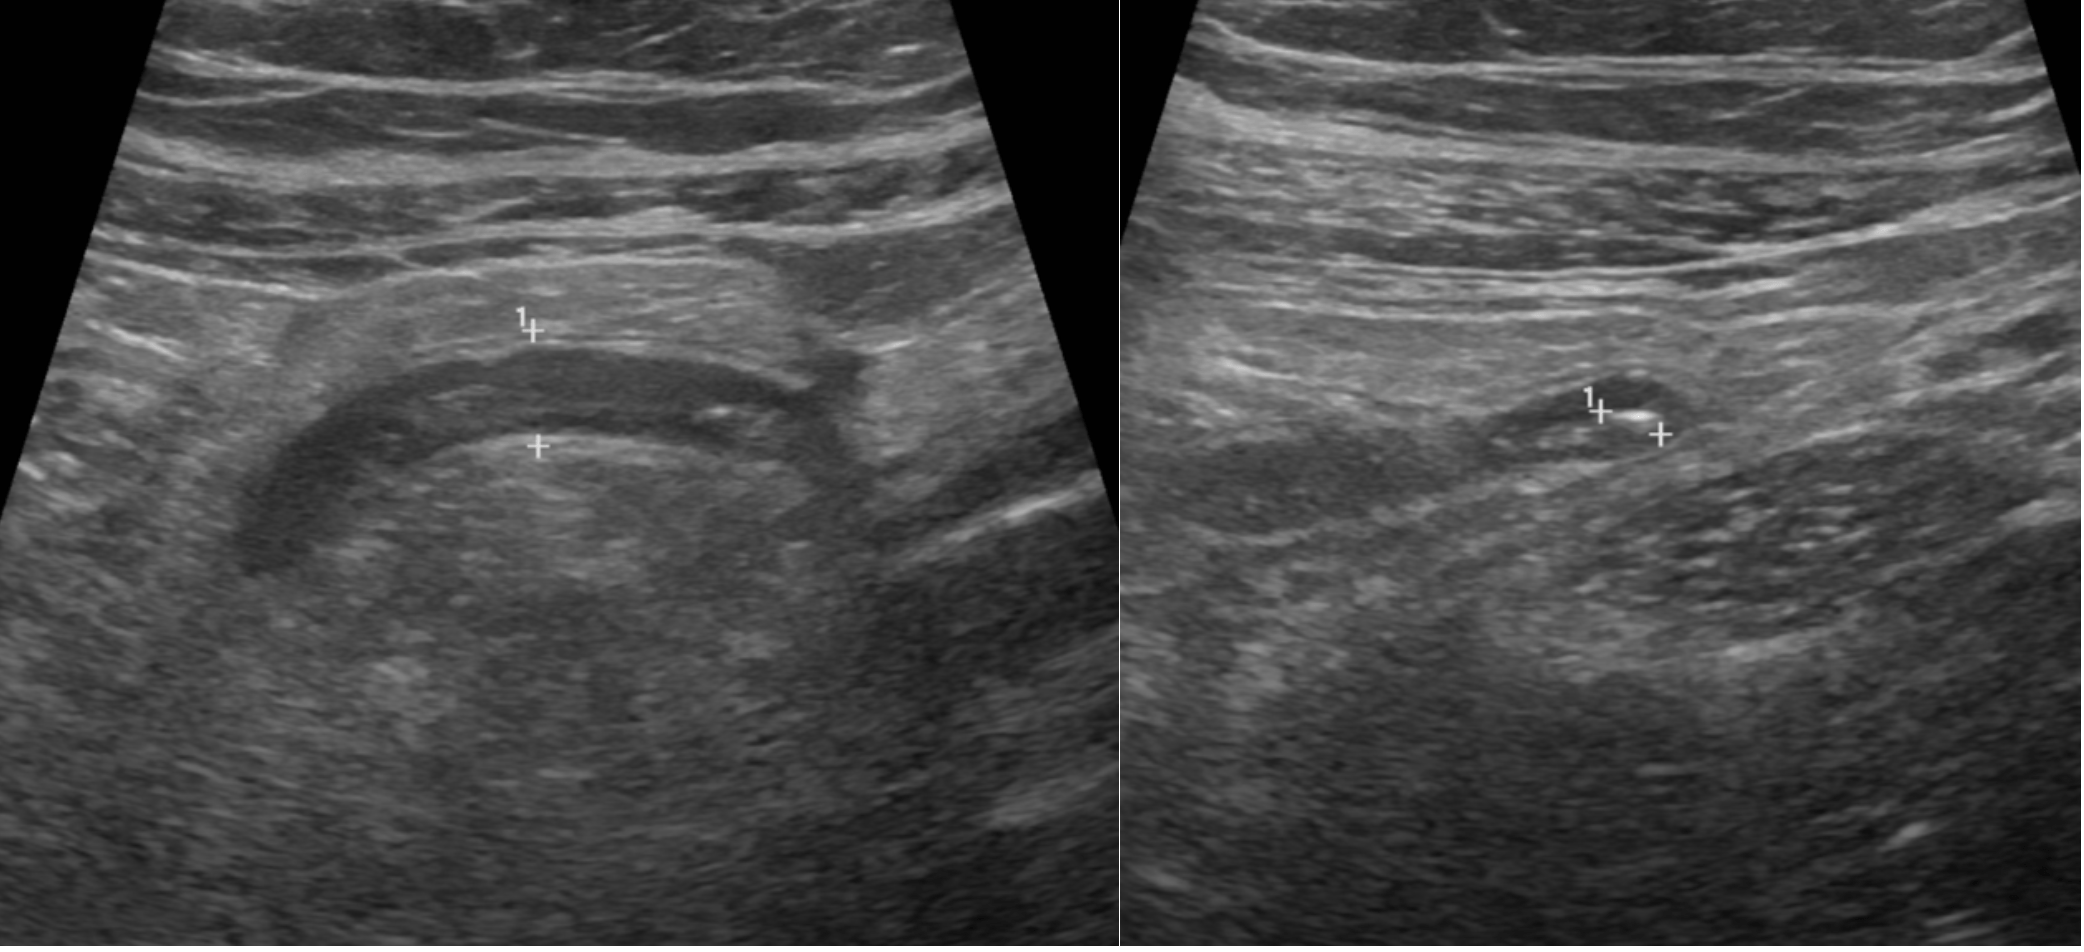

Atypical CEUS Pattern as a Diagnostic Clue in a Focal Liver Lesion [February 2026]

March 30, 2026